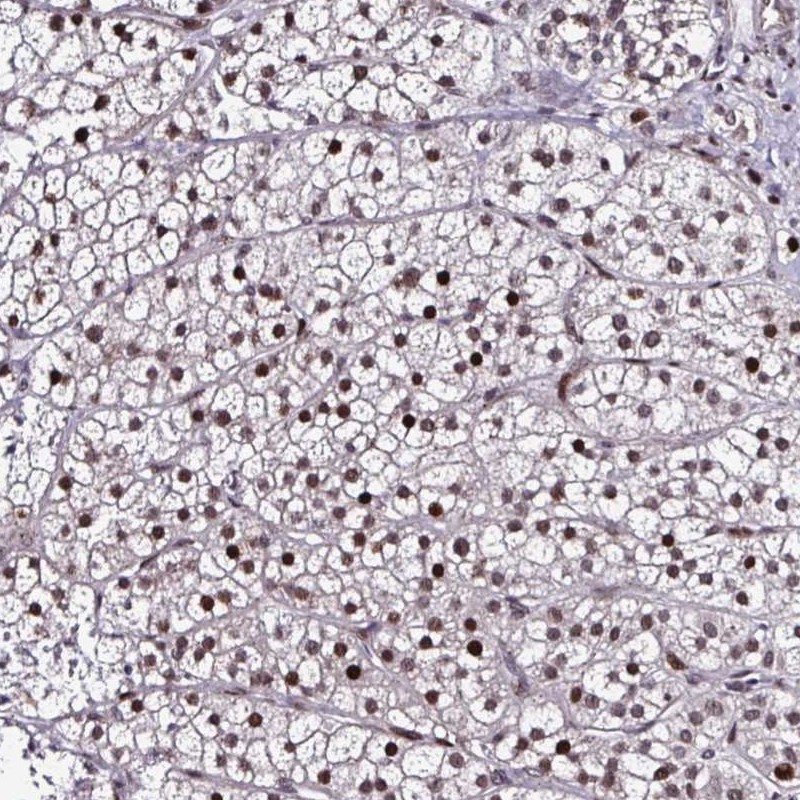

Immunohistochemical staining of human adrenal gland shows nuclear positivity in glandular cells.